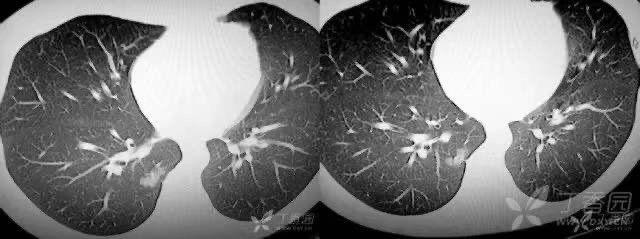

肺腺癌(MIA):左下肺可见磨玻璃结节,边缘清楚。可见血管进入,内可见空泡征。

腺癌:右肺下叶胸膜下磨玻璃结节灶,边缘分叶,可见胸膜牵拉征

炎性假瘤:女,45 岁, 查体发现肺内结节,轴面图像可见细支气管通过结节。